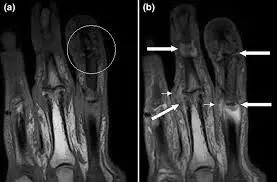

Psoriatic arthropathy is the asymmetrical oligoarthritis of psoriasis patients. It most commonly affects the distal interphalangeal joints and presents with fusiform (sausage-shaped) swelling of the digits with onycholysis (separation of the nails from the nail bed).

Image - An MRI scan of a patient with psoriatic arthropathy

Creative commons source by Fiona McQueen, Marissa Lassere and Mikkel Østergaard [CC BY-SA 4.0 (https://creativecommons.org/licenses/by-sa/4.0)]